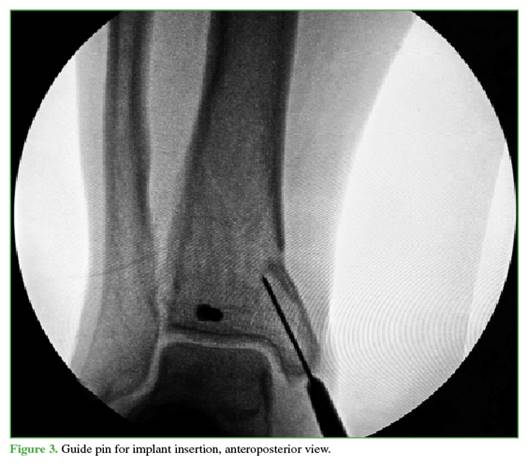

A 3 cm incision is then made distally from the tip of the tibial malleolus (Figure 2). Using a guidewire, the entry point is identified in the center of the tibial malleolus in both planes (Figures 3 and 4), and then enlarged with a cannulated reamer (Figure 5). An olive-tipped guidewire is inserted (Figure 6), and reaming of the medullary canal is performed through a soft tissue protector (Figure 7).